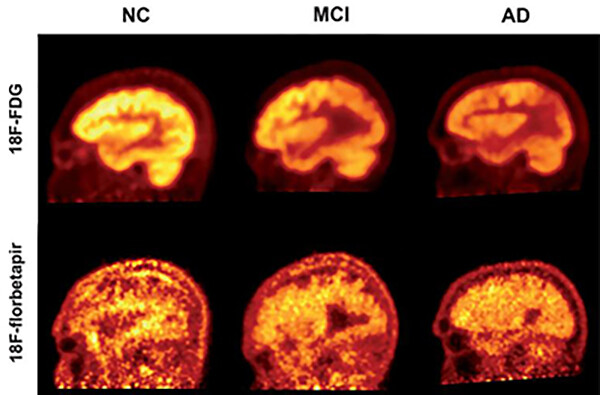

While the presence of beta-amyloid plaques in the brain may be a hallmark of Alzheimer’s disease, giving patients an amyloid PET scan is not an effective method for measuring their cognitive function, according to a new study from researchers in the Perelman School of Medicine and Thomas Jefferson University. The researchers concluded that fluorodeoxyglucose (FDG) PET, which measures the brain’s glucose consumption as a marker of neural activity, is a stronger approach for assessing the progression and severity of Alzheimer’s and mild cognitive impairment (MCI) as compared to florbetapir-PET scans, which reveal amyloid protein deposits in the brain. This suggests that FDG-PET is also a better means for determining the effectiveness of Alzheimer’s therapies, as well as tracking patients’ disease advancement, in both clinical and research settings. Results of this study are detailed in the August issue of the Journal of Alzheimer’s Disease.

“Both florbetapir-PET and FDG-PET are approved diagnostic methods for Alzheimer’s disease, and both appear to be effective in indicating some sort of cognitive impairment. However, we have now shown that FDG-PET is significantly more precise in clinical studies, and it is also available for routine use with modest costs,” says the study’s co-principal investigator Abass Alavi, a professor of radiology at Penn. “Our results support the notion that amyloid imaging does not reflect levels of brain function, and therefore it may be of limited value for assessing patients with cognitive decline.”

Two of the most significant biomarkers found in Alzheimer’s are decreased glucose uptake and the accumulation of amyloid plaques in the brain. PET scans use different radioactive drugs, called radiotracers, to measure these biomarkers within the brain tissue of patients with cognitive impairment. FDG-PET is one of the most commonly used imaging techniques to diagnose Alzheimer’s. However, in recent years, several other radiotracers, such as florbetapir, have been developed to detect the deposition of amyloid plaques.

Recently, the effectiveness of amyloid imaging as a strategy for monitoring dementia symptoms has been called into question.